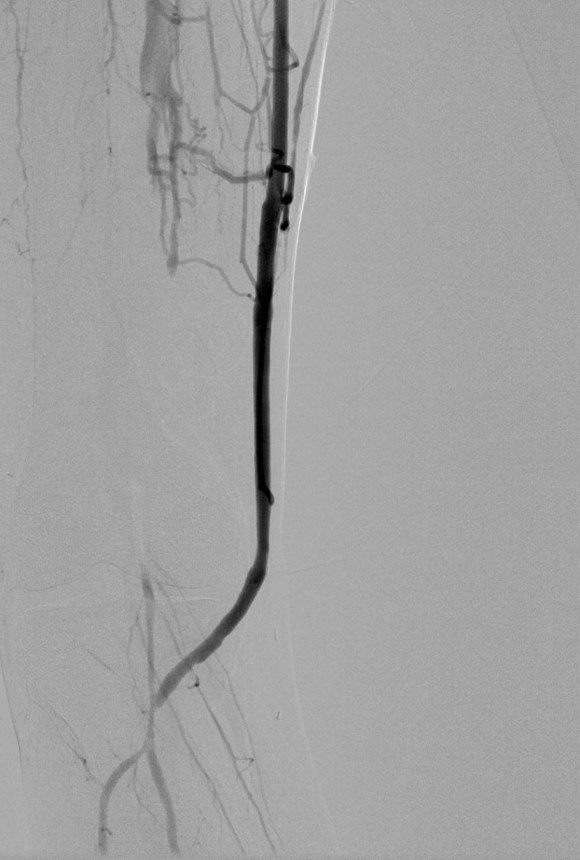

The purpose of the arteriogram is to evaluate the anatomy for treatable lesions. Screening for these lesions can be just as easily performed with handheld pulse Doppler and if needed, duplex ultrasound. In my experience, the triad of pink toes, palpable pedal pulses, and multiphasic signals in the distal anastomosis is more than enough evidence to start drying up and closing. In this particular case shown in the picture above, the anastomosis looked pristine, but the signals were weak and monophasic in the distal anastomosis despite palpable pulses. Arteriography reveals the reason below, but frankly, the arteriogram was dispensible even in this case (trainees –reason why?). In fact, arteriography takes care of the surgeon more than it does the patient. Tan et al [J Vasc Surg 2014;60:678-85] for the Vascular Study Group of New England, including my friend Dr. Alik Farber, reviewed the VSGNE database and found that a strategy of compulsive completion studies which included angiography or duplex ultrasonography, did not improve short term or 1 year graft patency.